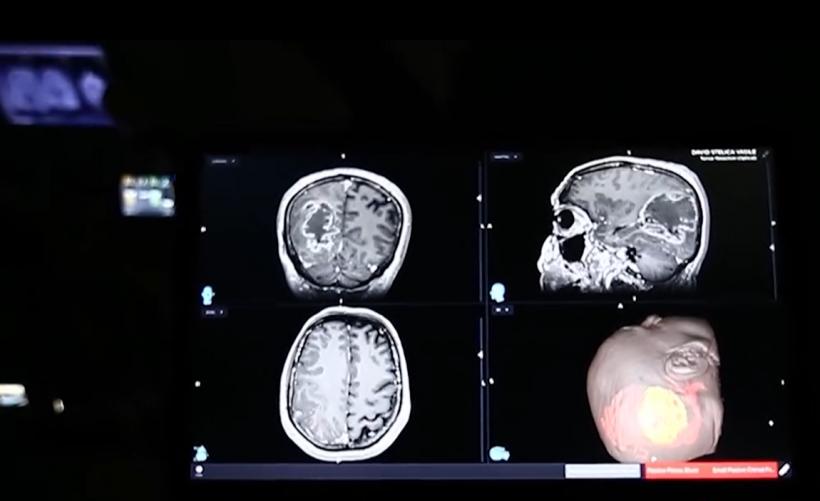

Lacrimi de fericire. Bărbat cu tumoră cerebrală gigant, operat cu succes la Spitalul „Nicolae Oblu” din Iași: E o minune | Galerie Foto | Imagine 2

Spitalul Clinic de Urgență "Prof. Dr. Nicolae Oblu" Iași